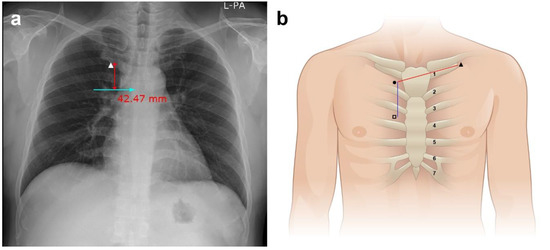

- Hsu, J.H.; Wang, S.S.; Lu, D.V.; Cheng, K.I.; Wang, C.K.; Wu, J.R. Optimal skin surface landmark for the SVC-RA junction in cancer patients requiring the implantation of permanent central venous catheters. Anaesthesia 2007, 62, 818–823. [Google Scholar] [CrossRef] [PubMed]